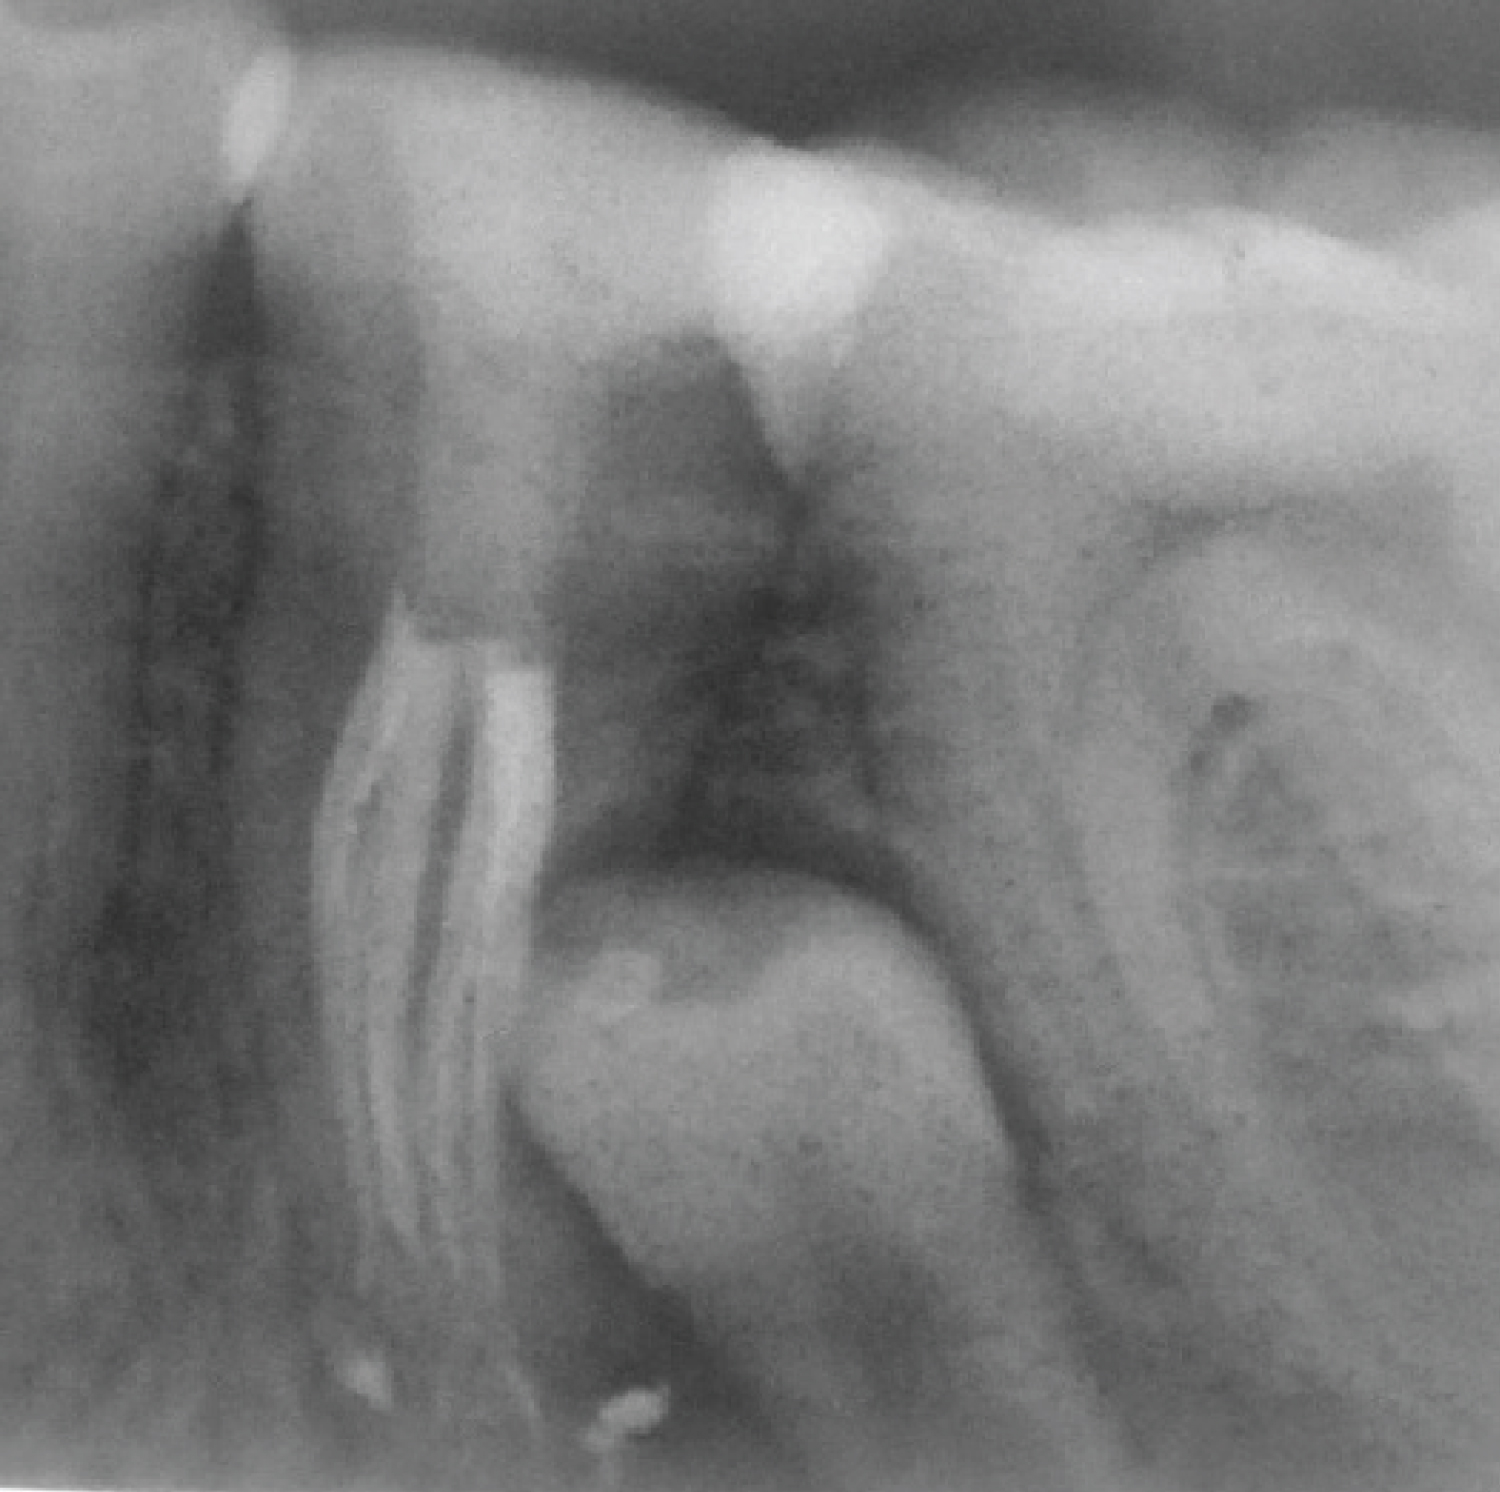

The working length was determined using an apex locater (Root ZX II, MORITA, JAPAN) and confirmed radiographically (Figure 6). Root canals were then prepared with Rotary endodontic file PROFILE®, 4% taper (Dentsply Maillefer, USA) using the step-down technique. The master file size was #25 Profile with 4% taper. The canals were thoroughly irrigated with 5% NaOCl solution (20 cc) and 17% ethylenediaminetetraacetic acid (10 cc). Root canals patency was maintained throughout the cleaning and shaping steps using size 10 K-file (Dentsply Maillefer, Ballaigues, Switzerland). Root canal filling was done using matching gutta-percha cones (Dentsply Maillefer, USA) and AH Plus sealer (Dentsply DeTrey GmbH, USA). The sealer was introduced into the canals by #20 K-file rotated in an anticlockwise direction. Then vertical compaction was performed to the level of the canal's trifurcation (Figure 7 and Figure 8). The root canal anatomy configuration is class VI according to Gulabivala and colleagues classification [17]. Root canal sealer puff was noticed apically and laterally in conjunction with the impacted premolar.

Figure 7: Distal angle periapical radiograph of tooth #35 after obturation. View Figure 7

Figure 8: Head on periapical radiograph of tooth #35 after obturation. View Figure 8